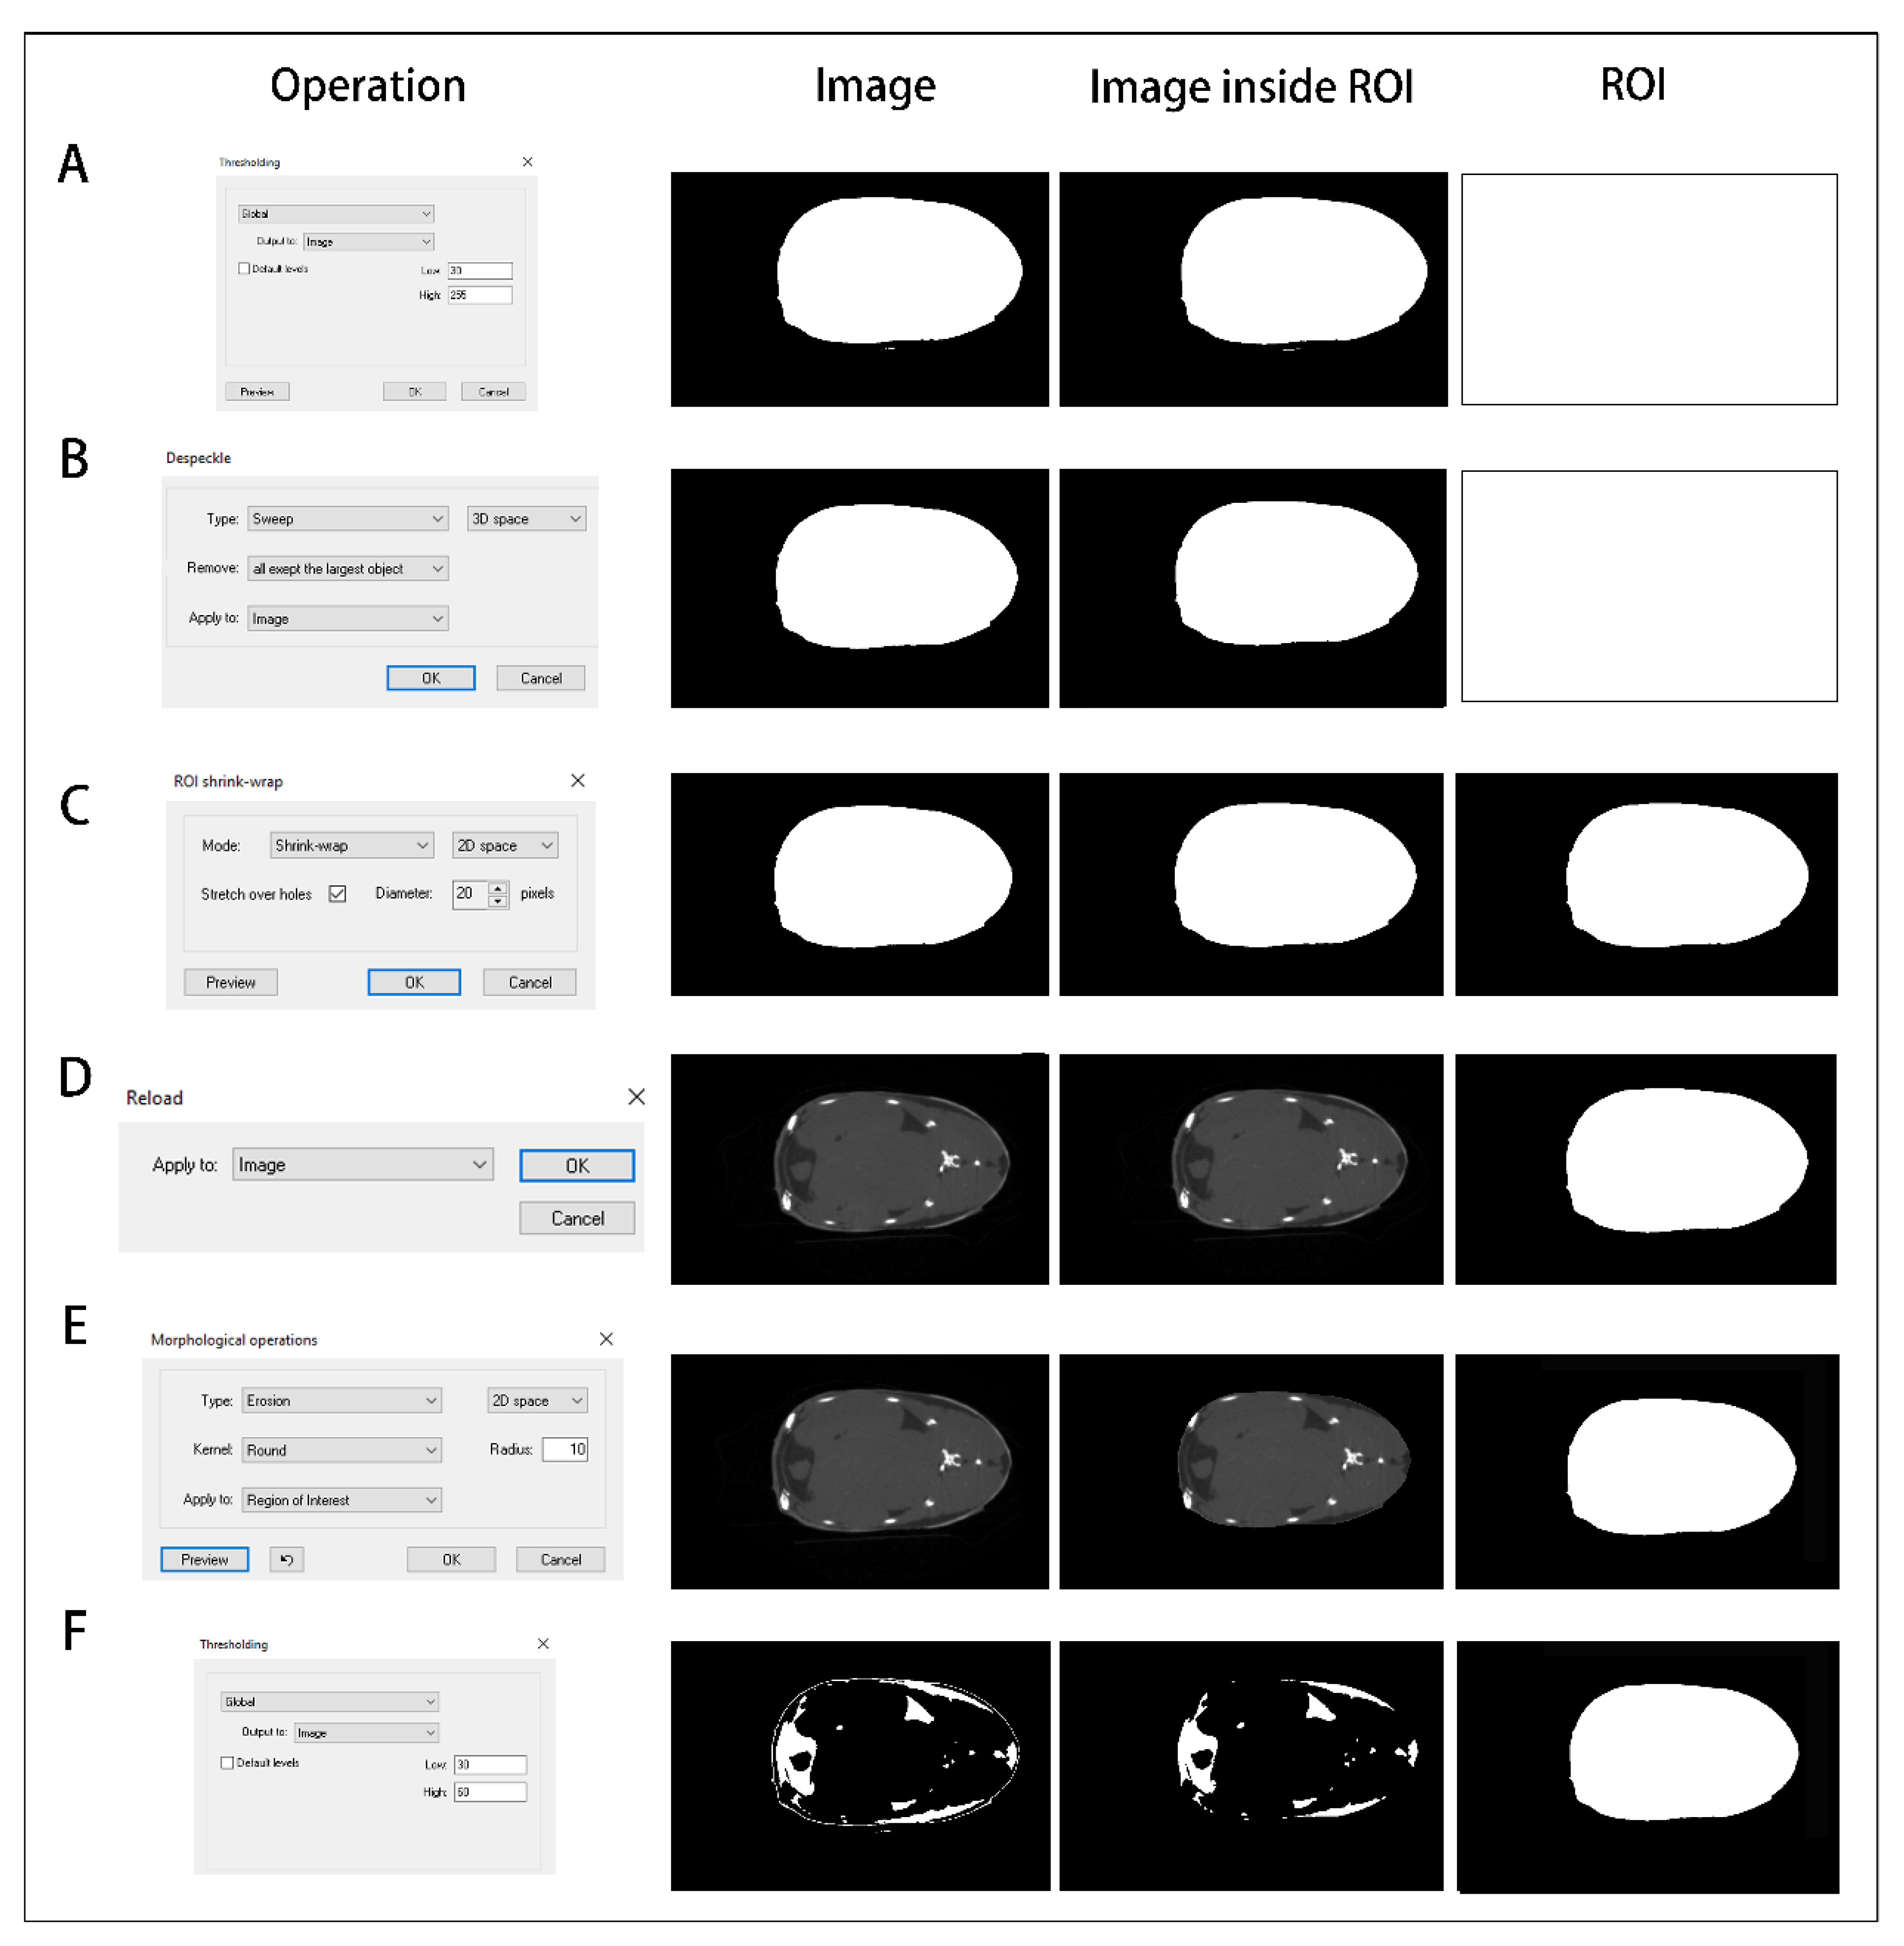

2.5. Data Processing

3.4. Quantitative Calculation of Trunk Adipose Tissue